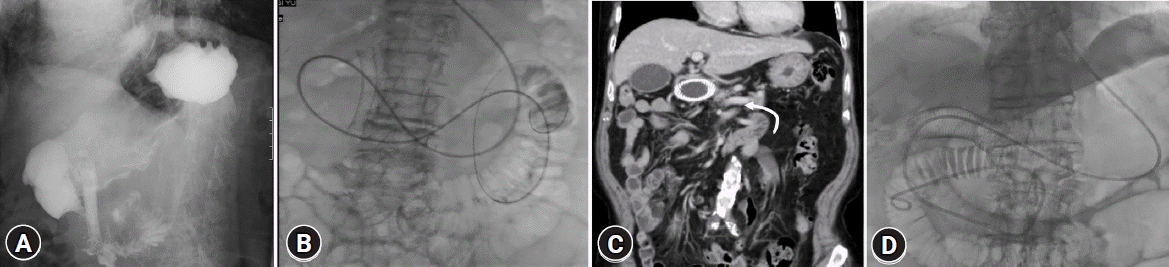

Comprehensive imaging studies are recommended before the EUS-GE procedure, including abdominal computed tomography and upper gastrointestinal (GI) series (Fig. 1), and are conducted to assess the length of the GOO and the anatomical relationship between the stomach and small intestine to predict the difficulty of performing EUS-GE.11 This approach excluded the possibility of multi-segment stenosis, peritoneal metastasis, or identification of any potential anatomical variations or complications, such as the presence of adhesions or a distorted anatomy due to previous surgeries.

Fig. 1.

(A) Upper gastrointestinal (UGI) series image shows the filling defect (tumor) is noted at the second portion of duodenum (type II gastric outlet obstruction). The direction and pattern of the proximal small intestine are visualized by the contrast media enhancement. (B) A 7-Fr nasobiliary catheter tube is inserted through the guidewire into the proximal jejunum. Saline and contrast media is infused through the nasobiliary drainage tube and the pattern of the small intestine is similar to that visualized by UGI series. (C) Abdominal computed tomography (CT) reveals the proximal jejunum goes to the right side after the small intestine passes through the ligament of Treitz. (D) The direction and pattern of the proximal jejunum is also similar with abdominal CT image.